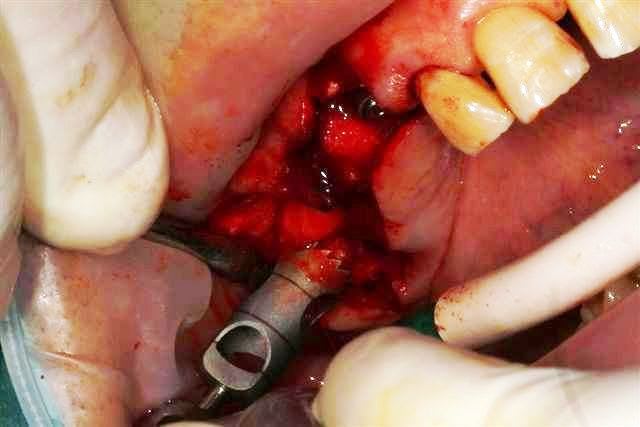

Ensuite zone 16 .. carottage, sciage en vest, carottage prélèvement de la carotte ajustage (délicat ça glisse:-)))

sur 2 ième et la troisième photo, tu utilises le disque pour pouvoir faire levier et sortir la carotte ?

Dans un premier temps oui, mais l'os etait trop "raide" donc j'ai repris la scie cloche en perpendiculaire.